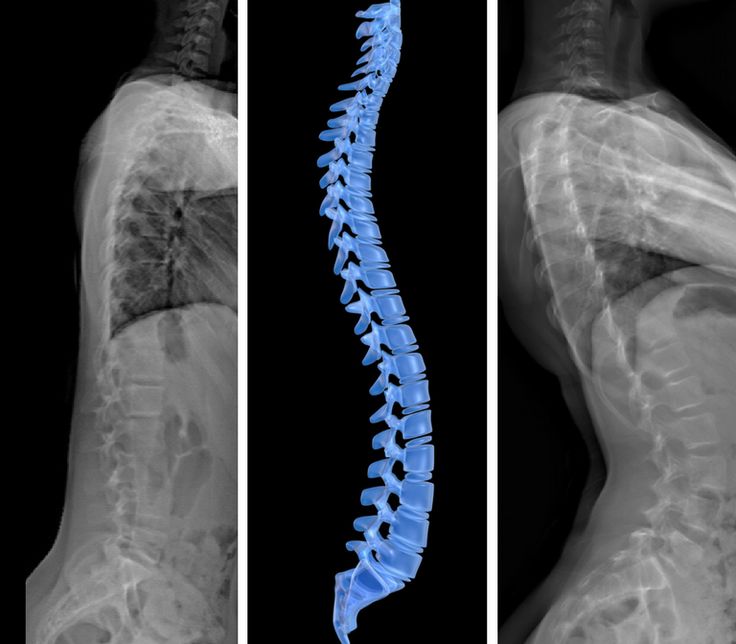

Bel fıtığı başta kollar olmak üzere, vücudun pek çok yerinde kuvvet kaybına, uyuşukluğa ve ağrıya neden olabilir. Bel

Bel fıtığı başta kollar olmak üzere, vücudun pek çok yerinde kuvvet kaybına, uyuşukluğa ve ağrıya neden olabilir. Bel fıtığı vakalarında düzenli egzersiz ve fizik